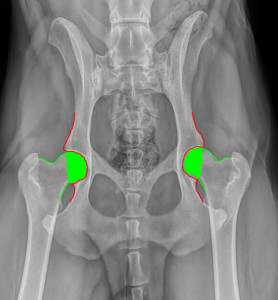

זה צילום אגן נורמלי כאשר העצמות הירך נמצאים בדיוק בתוך המשקע של האגן